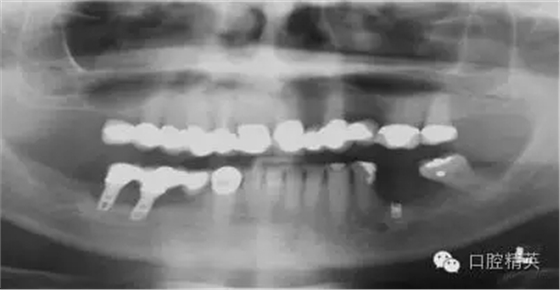

另一個和醫(yī)生僅用兩維放射線檢查造成的特殊并發(fā)癥是種植體進入上頜竇。(圖2a-c)可能成為上頜竇異物的有牙齒,牙根,印模材料,牙科器械,近年來又增加了一個—種植體。可想而知,從上頜竇中取出異物對患者來講是創(chuàng)傷很大的。

其他研究也報道過,對于這種病例,唯一的選擇是用根管顯微鏡或Caldwell Luc技術(shù)從上頜竇中取出種植體。有些文章報道了如何處理進入上頜竇的種植體,但很少從預(yù)防的角度來談這個問題,其實很簡單,術(shù)前應(yīng)該應(yīng)用CBCT成像檢查。

圖3a:術(shù)后的三維影像重建給外科醫(yī)生對手術(shù)入路的回顧以提示。對于這一病例進行了Caldwell-Luc術(shù)式,用球鉆在上頜竇側(cè)壁做一窗口,直接入路取出種植體。